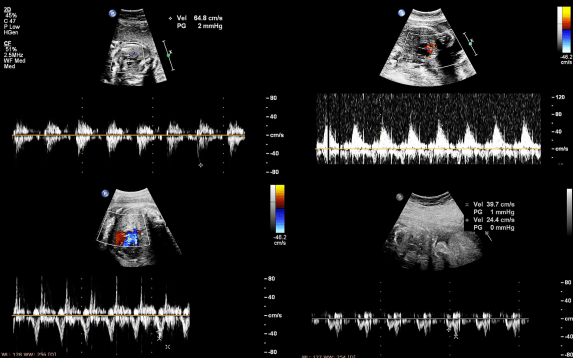

Fetal echocardiography, also known as fetal cardiology, is a specialized ultrasound used to study the baby’s heart during pregnancy. It provides a detailed view of the heart’s structure, rhythm, and function. This test helps detect congenital heart defects early, allowing doctors to plan appropriate care before birth. It is usually recommended between 18 and 24 weeks of pregnancy.

The procedure is similar to a standard ultrasound. A transducer is gently moved over the abdomen to capture detailed images of the baby’s heart. The test is painless and completely safe for both mother and baby. Using advanced ultrasound machines, doctors can see the heart’s chambers, valves, and blood flow in real time, ensuring a precise evaluation.